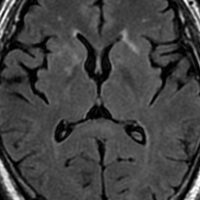

てんかんの薬を止めた時のMERS

mild encephalitis/encephalopathy with a reversible isolated SCC (splenium) lesionといいます。グリオーマの患者さんで予防的に抗てんかん薬を処方することは多いです。腫瘍が落ち着いて長くてんかん発作がない時には,抗てんかん薬を中断します。その時に,MRIで脳梁膨大部 splenium というところに異常な初見が出てグリオーマの再発と間違うことがあります。でもこれはMERSという一時的な病変で,何もしないでも消失します。

左が拡散強調画像 DWIで脳梁膨大部が高信号で白く見えます。右はFLAIR画像でよく見るとちょっとだけ白く見えます。この例はとても軽い初見でDWIでしかはっきりしませんが,通常はFLAIR画像で楕円形の病変としてみられます。